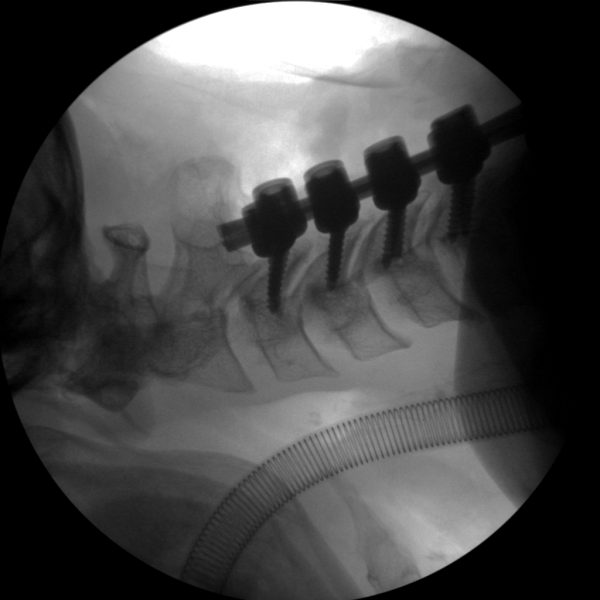

Skan-C uses advanced imaging technology, such as pulsed fluoroscopy and digital subtraction angiography, to provide highly detailed images of the affected area. This allows doctors to perform procedures with increased precision and accuracy, and better patient outcome

Clinical Evidence

Skan-C is a great C-arm for neurology treatments for several reasons